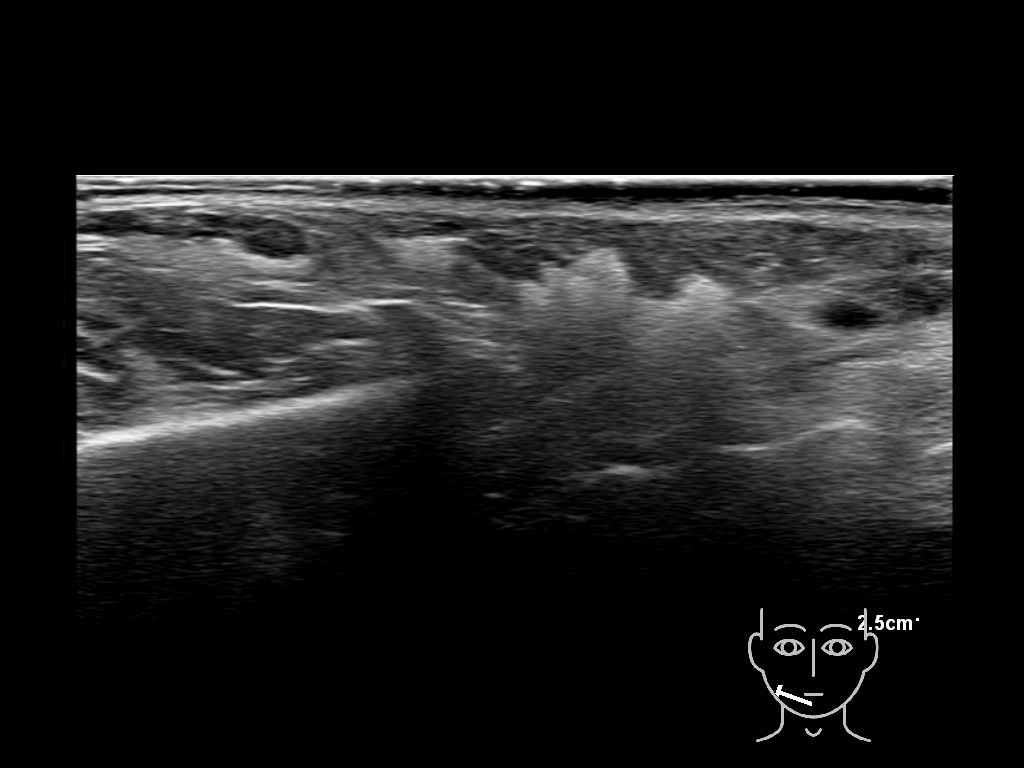

HACa 5b e